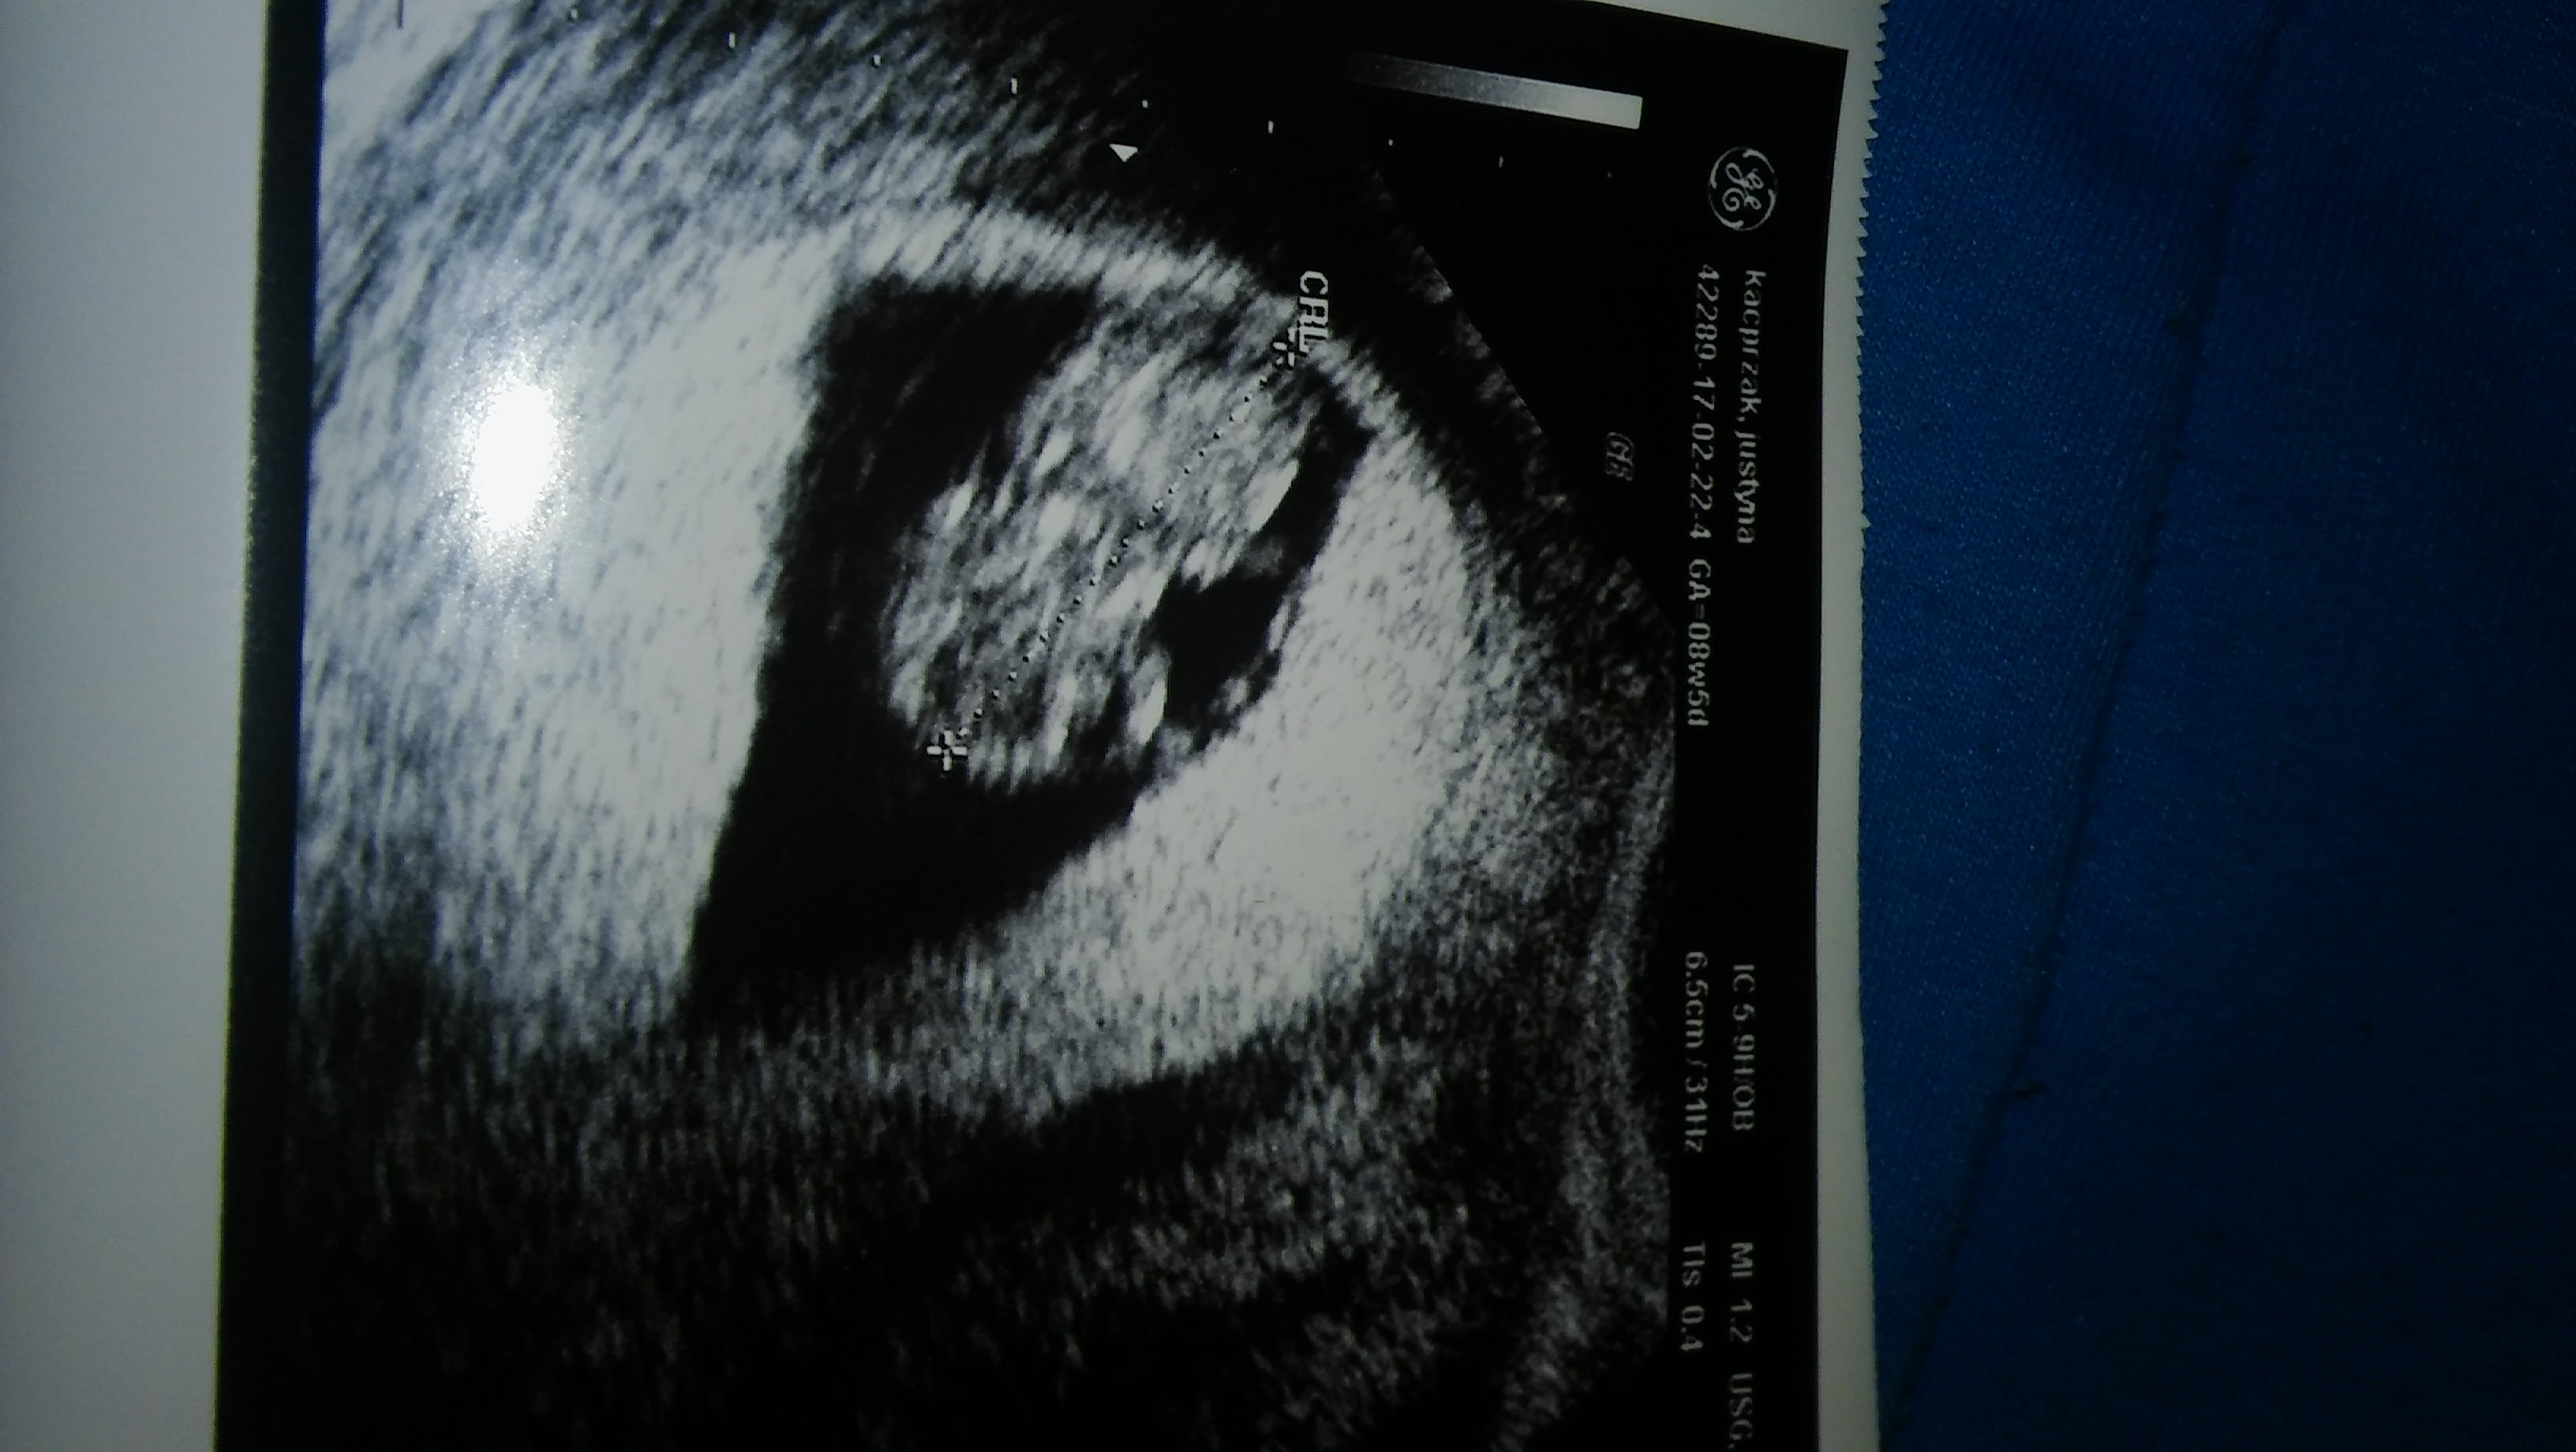

Ja z moim mam to samo... Niczym si nie interesuje, nie pyta jak się czuję, nawet nie obejrzał dzisiejszego o Zdjęcia z USG. Co wieczór się z nim kłócę, żeby zmienił podejście, żeby poczytał o tych wszystkich zmianach jakie zachodzą w moim ciele, żeby spróbował zrozumieć moje zmiany nastrojów i to wszystko co się dzieje, a on nic... Nigdy bym nie pomyślała, że taki się zrobi... Jak nie on...